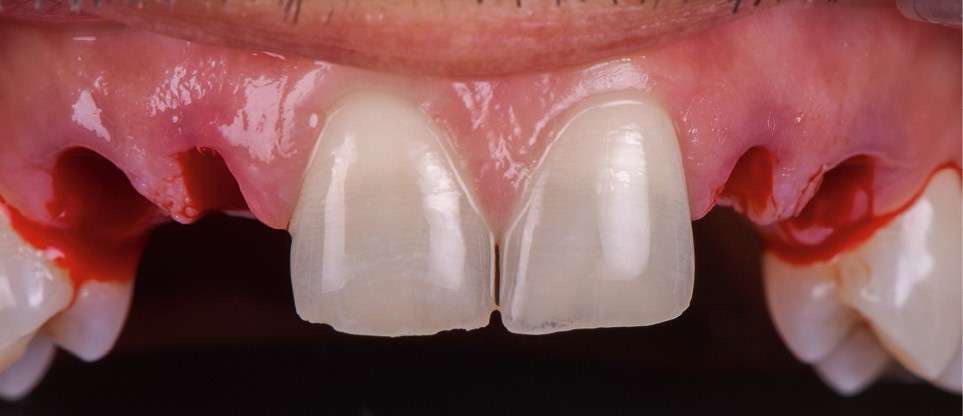

- extraction des dents 52 53 62 63 de manière « atraumatique » (fig. 3) ;

- pose des couronnes d’usage selon le protocole classique (fig. 9 et 10a) ;